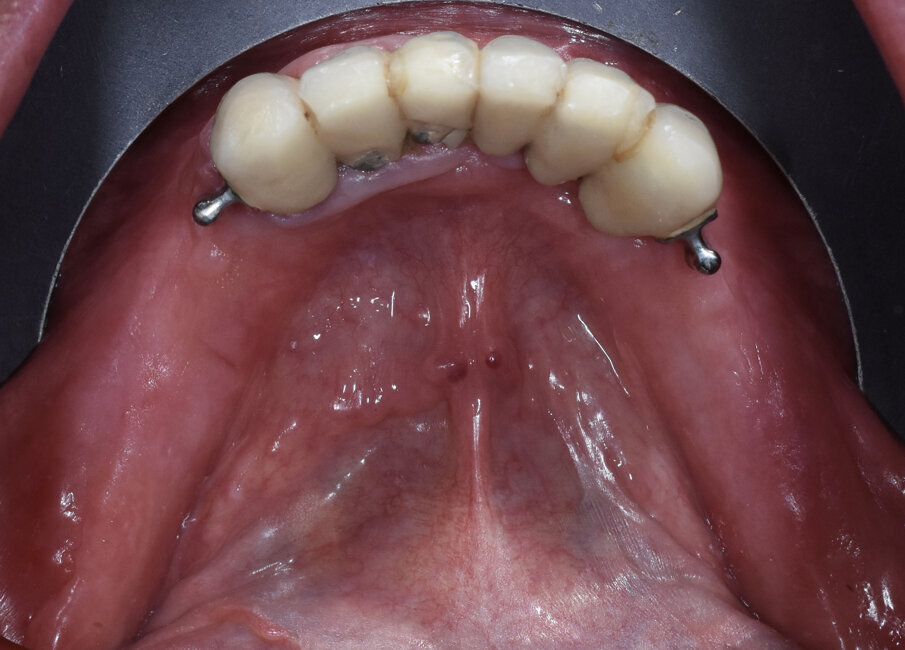

Fig. 3 - Visione occlusale.

Fig. 10 - Visione occlusale.

Fig. 20 - Visione occlusale provvisorio.